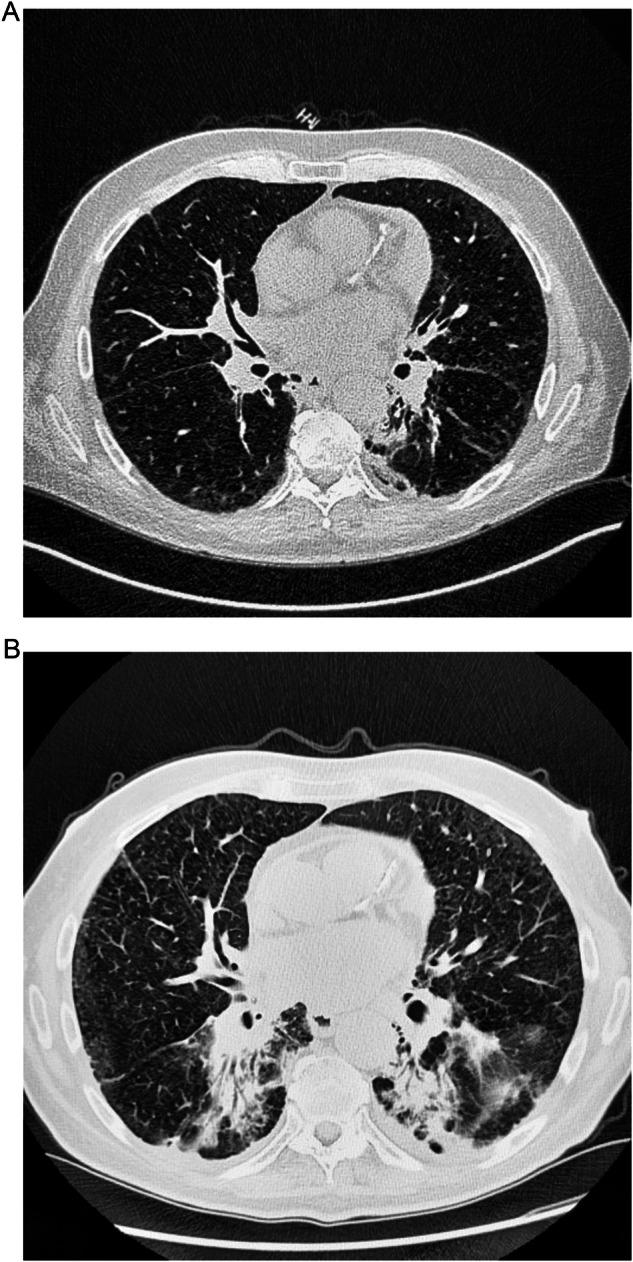

Systemic anticancer therapies (SACTs) are the leading cause of drug-induced interstitial lung disease (ILD). As more novel SACTs become approved, the incidence of this potentially life-threatening adverse event (AE) may increase. Early detection of SACT-related ILD allows for prompt implementation of drug-specific management recommendations, improving the likelihood of AE resolution and, in some instances, widening the patient's eligibility for future cancer treatment options. ILD requires a diagnosis of exclusion through collaboration with the patient's multidisciplinary team to rule out other possible etiologies of new or worsening respiratory signs and symptoms. At Grade 1, ILD is asymptomatic, and thus the radiologist is key to detecting the AE prior to the disease severity worsening. Planned computed tomography scans should be reviewed for the presence of ILD in addition to being assessed for tumor response to treatment, and when ILD is suspected, a high-resolution computed tomography (HRCT) scan should be requested immediately. An HRCT scan, with < 2-mm slice thickness, is the most appropriate method for detecting ILD. Multiple patterns of ILD exist, which can impact patient prognosis. The four main patterns include acute interstitial pneumonia / acute respiratory distress syndrome, organizing pneumonia, hypersensitivity pneumonitis, and non-specific interstitial pneumonia; their distinct radiological features, along with rarer patterns, are discussed here. Furthermore, HRCT is essential for following the course of ILD and might help to determine the intensity of AE management and the appropriateness of re-challenging with SACT, where indicated by drug-specific prescribing information. ILD events should be monitored closely until complete resolution. CRITICAL RELEVANCE STATEMENT: The incidence of potentially treatment-limiting and life-threatening systemic anticancer therapy-related interstitial lung disease (SACT-related ILD) events is likely increasing as more novel regimens become approved. This review provides best-practice recommendations for the early detection of SACT-related ILD by radiologists. KEY POINTS: Radiologists are crucial in detecting asymptomatic (Grade 1) ILD before severity/prognosis worsens. High-resolution computed tomography is the most appropriate method for detecting ILD. Drug-induced ILD is a diagnosis of exclusion, involving a multidisciplinary team. Familiarity with common HRCT patterns, described here, is key for prompt detection. Physicians should highlight systemic anticancer therapies (SACTs) with a known risk for interstitial lung diseases (ILD) on scan requisitions.